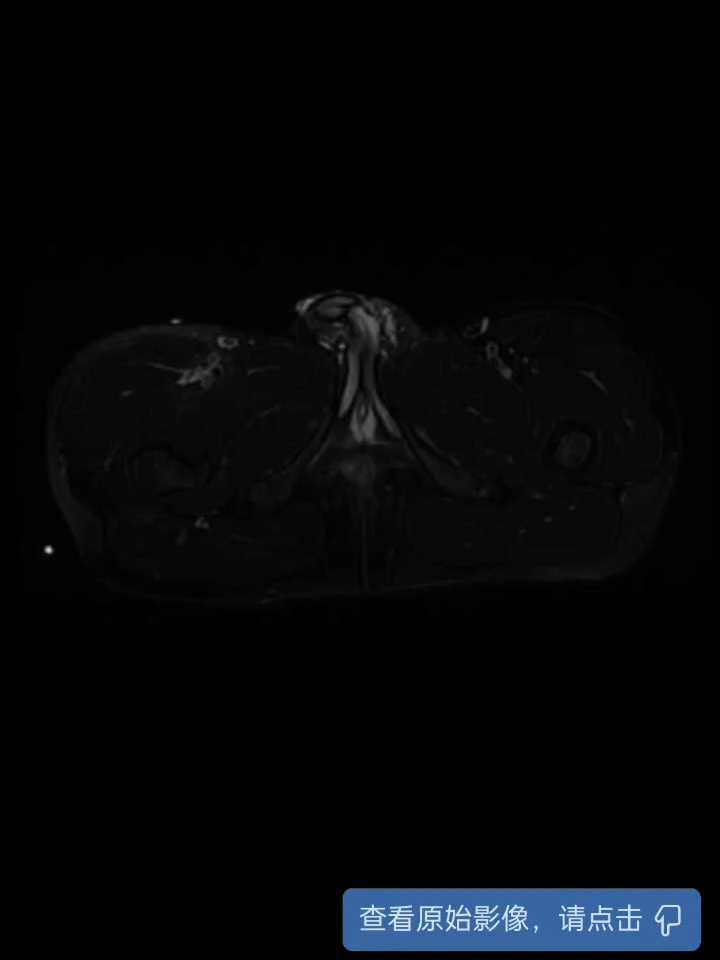

盆腔增强CT

磁共振增强